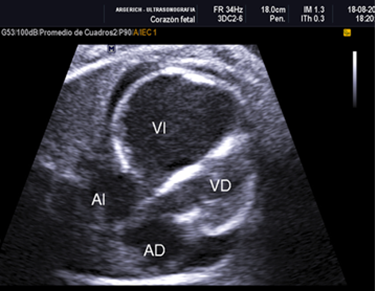

Por tal hallazgo se solicita ecocardiografía fetal a la unidad de Medicina fetal que reporta:1) Engrosamiento hiperecogenico endocárdico del ventrículo izquierdo dilatado con disfunción diastólica severa, motilidad ventricular casi ausente compatible con fibroelastosis endocárdica (Figura Nº1). 2) Desviación del tabique interventricular al lado derecho con dos comunicaciones interventriculares pequeñas cerca del ápex. 3) Derrame pericárdico de 3 mm en relación a la pared posterior del VI. 4) tractos de salida y entrada normales. También se solicita Doppler obstétrico observándose hemodinamia feto-placentaria y útero-placentaria normal (Figura 1).

Los hallazgos ecográficos, en el caso de fibroelastosis del ventrículo izquierdo, muestran las paredes de este dilatadas e hiperecogénicas, en caso de estenosis aórtica la válvula aórtica aparenta estar engrosada, con dilatación postestenótica. Su diagnóstico definitivo se realiza mediante la biopsia del ventrículo izquierdo 9.